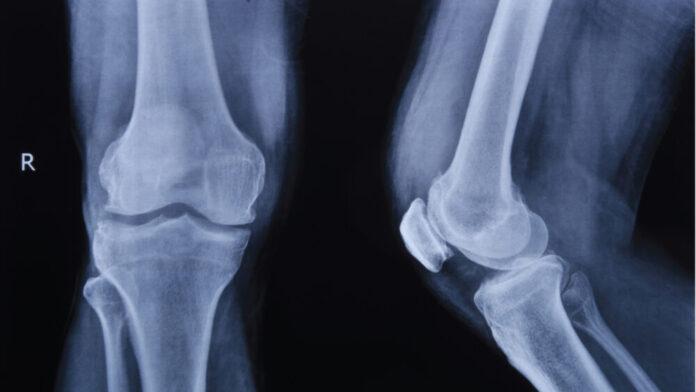

การแยกความแตกต่างระหว่างข้อเข่าเสื่อมกับอาการบาดเจ็บ จำเป็นต้องอาศัยการประเมินจากแพทย์เฉพาะทางกระดูกและข้อ ตั้งแต่การซักประวัติอย่างละเอียด การตรวจร่างกาย ไปจนถึงการตรวจทางรังสี เช่น X-ray เพื่อประเมินการเสื่อมของข้อ หรือ MRI เพื่อดูความเสียหายของเอ็นและโครงสร้างอ่อนภายในข้อ ซึ่งช่วยให้สามารถวางแผนการรักษาได้อย่างแม่นยำ